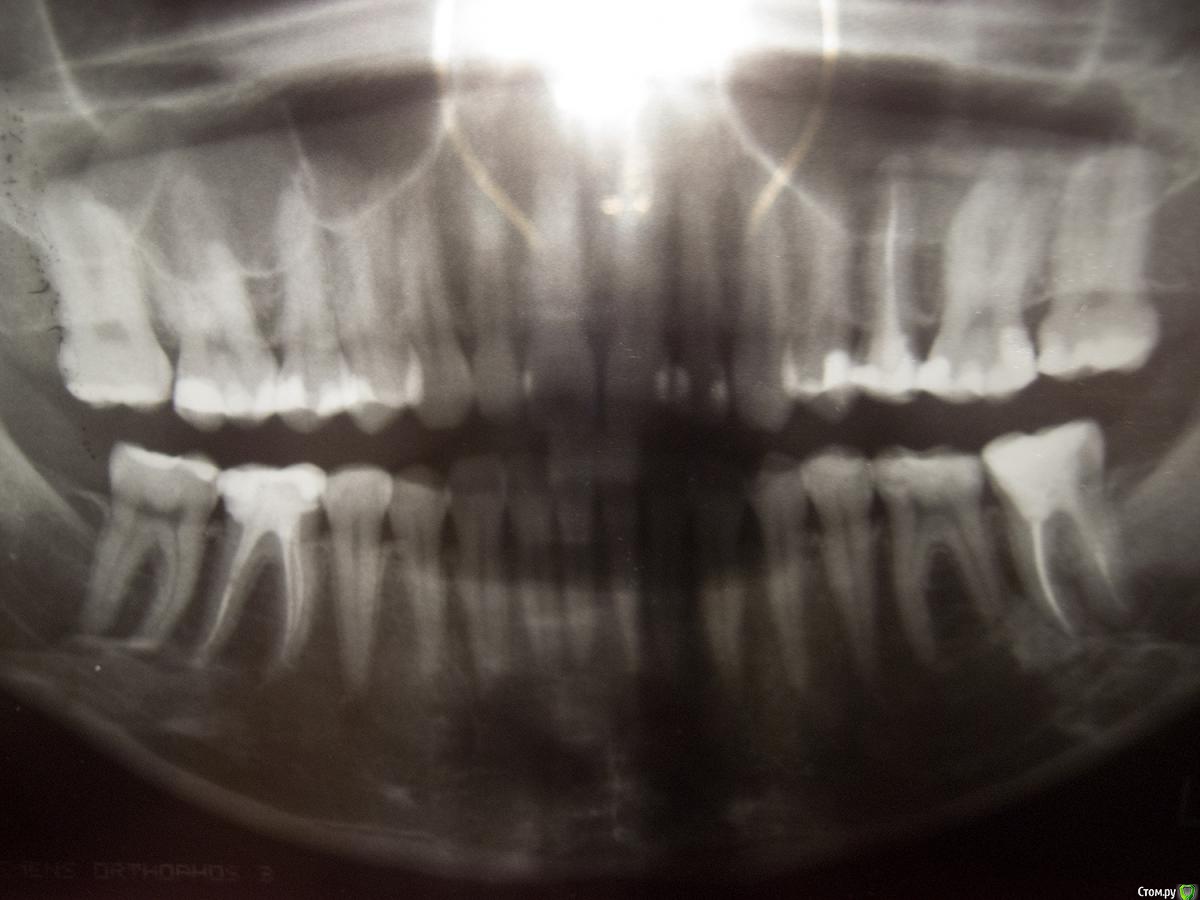

ptichka Опубликовано 2 марта, 2015 Автор Поделиться Опубликовано 2 марта, 2015 http://forum.stom.ru/topic/20613-sovety-patcientam-obiazatelno-k-prochteniiu/ Извините, пошла сделала рентген, но качество снимка оставляет желать лучшего (действительно такое качество, лучше не сфотографировать). Дело в качестве снимка, или все так плохо? Переделывать снимок есть резон (это уже второй рентген и так за последний год)? Пожалуйста, подскажите что-нибудь, очень переживаю на эту тему. Ссылка на комментарий

krokomot Опубликовано 2 марта, 2015 Поделиться Опубликовано 2 марта, 2015 Судя по снимку и фотографиям у вас все в порядке, разве что чистите неправильно зубы. Беспокоится особенно не о чем. 1 Ссылка на комментарий

DmitrySH Опубликовано 3 марта, 2015 Поделиться Опубликовано 3 марта, 2015 Подозрения,что у депульпированых зубов слева есть хроническое воспаление. Но настолько не четко, что по данному снимку сложно говорить. 1 Ссылка на комментарий

DmitrySH Опубликовано 4 марта, 2015 Поделиться Опубликовано 4 марта, 2015 Мотивация для снимков - исключить/ подтвердить развитие воспаления, которое в последствии может перерасти в кисту. Дальше продолжать? 1 Ссылка на комментарий